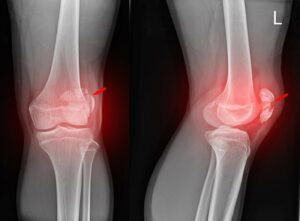

Điều trị u xương dạng xương hướng dẫn của chụp số hoá xoá nền

ĐẠI CƯƠNG U dạng xương là một u xương lành tính, thường xuất hiện ở...